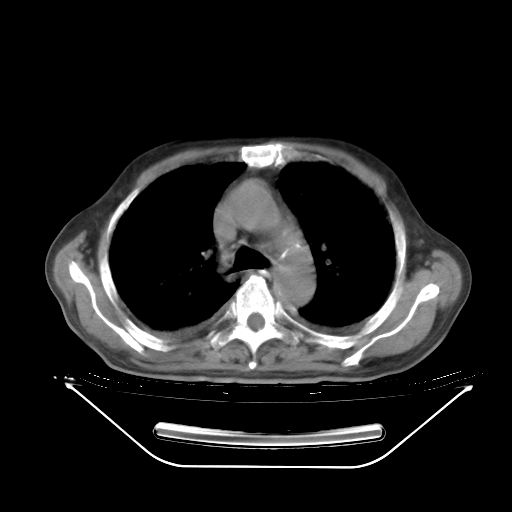

胸腹部CT,诊断意见:左上肺叶钙化灶、左侧胸膜局限性增厚并钙化、胆囊炎。描述部分肺组织呈磨玻璃样改变。